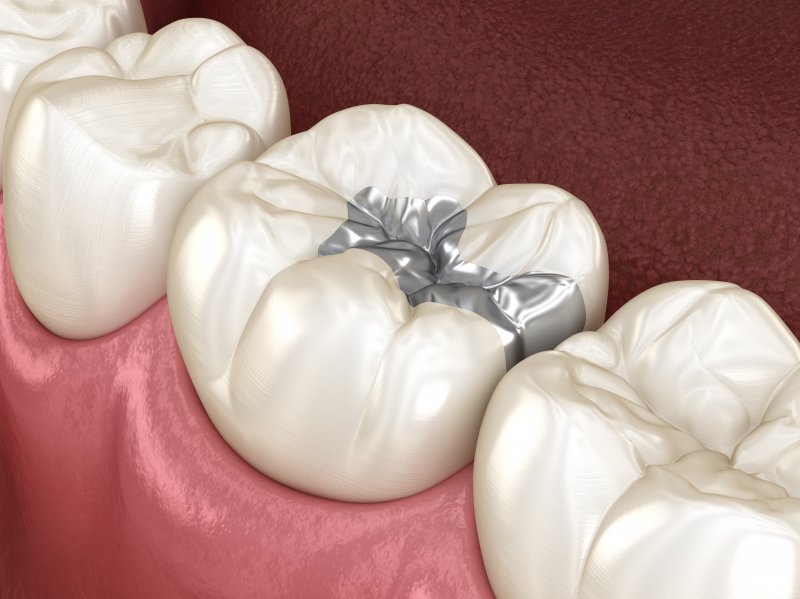

Why Replace Metal Fillings . amalgam fillings are the main source of inorganic mercury exposure (besides occupational exposure) for people with these kinds. Most often, it is the result of. There are several reasons why your filling may need to be replaced over time. understanding when and why to replace. can you replace silver fillings with white fillings? Over time, the seal connecting the. It is a relatively common procedure to replace amalgam fillings. why does my filling need to be replaced? what are amalgam dental fillings and why are they controversial? one of the primary reasons for replacing amalgam fillings is the development of new decay around the existing filling.

There are several reasons why your filling may need to be replaced over time. what are amalgam dental fillings and why are they controversial? one of the primary reasons for replacing amalgam fillings is the development of new decay around the existing filling. amalgam fillings are the main source of inorganic mercury exposure (besides occupational exposure) for people with these kinds. Over time, the seal connecting the. Most often, it is the result of. It is a relatively common procedure to replace amalgam fillings. understanding when and why to replace. why does my filling need to be replaced? can you replace silver fillings with white fillings?

Why Replace Metal Fillings Over time, the seal connecting the. why does my filling need to be replaced? Over time, the seal connecting the. what are amalgam dental fillings and why are they controversial? understanding when and why to replace. amalgam fillings are the main source of inorganic mercury exposure (besides occupational exposure) for people with these kinds. Most often, it is the result of. It is a relatively common procedure to replace amalgam fillings. can you replace silver fillings with white fillings? There are several reasons why your filling may need to be replaced over time. one of the primary reasons for replacing amalgam fillings is the development of new decay around the existing filling.